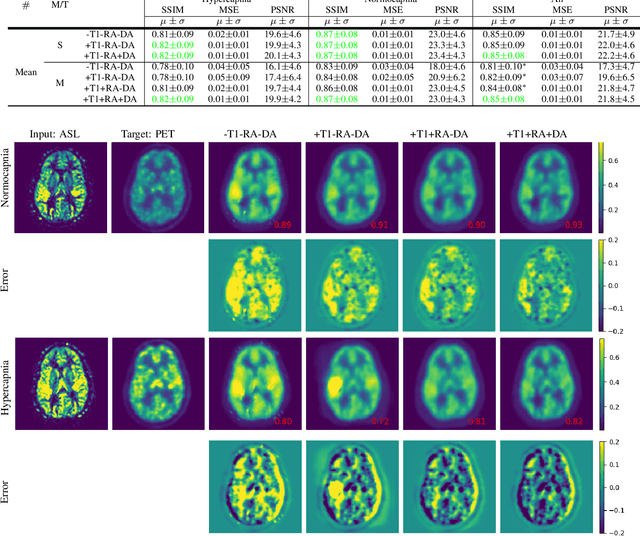

Abstract:Positron Emission Tomography (PET) is an imaging method that can assess physiological function rather than structural disturbances by measuring cerebral perfusion or glucose consumption. However, this imaging technique relies on injection of radioactive tracers and is expensive. On the contrary, Arterial Spin Labeling (ASL) MRI is a non-invasive, non-radioactive, and relatively cheap imaging technique for brain hemodynamic measurements, which allows quantification to some extent. In this paper we propose a convolutional neural network (CNN) based model for translating ASL to PET images, which could benefit patients as well as the healthcare system in terms of expenses and adverse side effects. However, acquiring a sufficient number of paired ASL-PET scans for training a CNN is prohibitive for many reasons. To tackle this problem, we present a new semi-supervised multitask CNN which is trained on both paired data, i.e. ASL and PET scans, and unpaired data, i.e. only ASL scans, which alleviates the problem of training a network on limited paired data. Moreover, we present a new residual-based-attention guided mechanism to improve the contextual features during the training process. Also, we show that incorporating T1-weighted scans as an input, due to its high resolution and availability of anatomical information, improves the results. We performed a two-stage evaluation based on quantitative image metrics by conducting a 7-fold cross validation followed by a double-blind observer study. The proposed network achieved structural similarity index measure (SSIM), mean squared error (MSE) and peak signal-to-noise ratio (PSNR) values of $0.85\pm0.08$, $0.01\pm0.01$, and $21.8\pm4.5$ respectively, for translating from 2D ASL and T1-weighted images to PET data. The proposed model is publicly available via https://github.com/yousefis/ASL2PET.